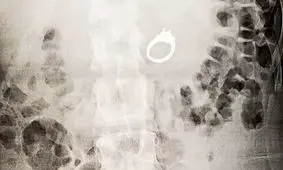

یک زن که اخیرا نامزد کرده است در حین خواب حلقه نامزدی خود را بلعید. این اتفاق باعث شد وی دچار اختلالاتی در سیستم گوارش…